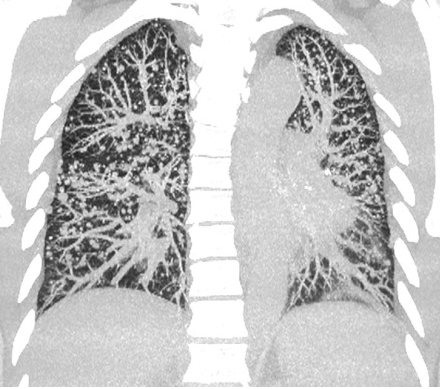

▲ 肺内结节、无处隐藏

我们知道,辐射是很多人担心的问题之一。飞利浦Incisive AI CT拥有不限体型、不限部位的临床化低剂量成像,大幅抑制噪声的同时提高图像对比度,保障图像质量满足临床诊断要求。